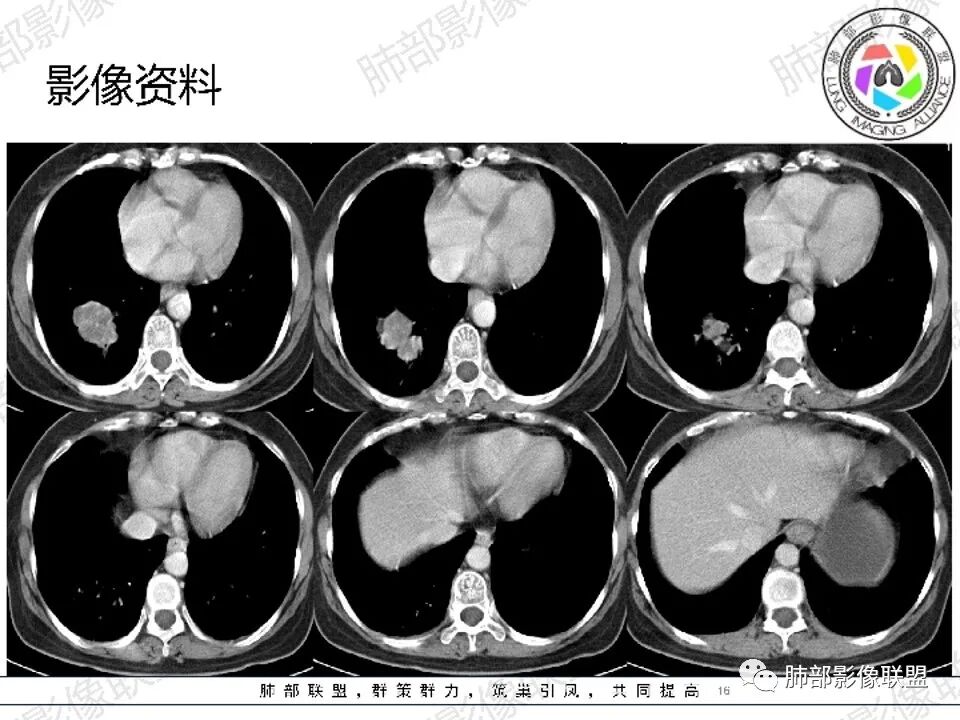

左肺门肿块,不均一强化,分叶,钙化,支气管堵塞,首先考虑直肠癌转移

必有路: 女性,中老年人,3年前直肠癌,如今体检发现右肺下叶团块,分叶,边清,无毛刺,无晕,强化不均,内部坏死,无支气管堵,无淋巴结肿大诊断:倾向恶性,转移瘤可能鉴别:原发肿瘤(神经内分泌癌>腺)建议:查肿瘤指标,尤其cea,追问原来直肠癌病理类型,活检

361度:

中年女性,既往直肠癌手术病史,现发现右肺下叶肿块,似两个结节融合。边缘膨隆,支气管阻塞,增强扫描不均匀强化,内血管影边缘模糊。考虑气道转移性肿瘤,鉴别肺原发肿瘤。

金豆 (刘权威): 右肺下叶类圆形结节,膨胀性生长,边缘清,浅分叶,轻度强化,内可见坏死,似乎坏死不太彻底,坏死边缘模糊,考虑恶性,腺癌,鉴别鳞,寡转移(既往直肠癌病史)。

空格: 中年女性,结肠术后3年,转移的高发时段。胸部无症状,有肿瘤偷袭风险。影像特点。1 感觉不是一个结节(蘑菇兄弟?),有强化的分隔,血行转移单克隆膨胀生长应该可以排除。2 病灶有沿支气管扇形分布,有沿支气管生长的可能,有结肠癌支气管内膜转移的可能   3 病灶低强化,有坏死,结肠癌转移一般强化较明显。不知道病人术后有没有放化疗,引起的低免疫状态,是否存在机会感染的可能。支气管内膜转移的发生率极低,从概率的角度。我的排序:鳞癌》隐球菌(结核)》支气管内膜转移。

必有路: 影像不像原发腺 女性鳞少,支持转移,3年前手术,必定有胸部检查,下肺,扫腹部ct也会看到,即便没有胸部ct,3年前无,现在有,小细胞不像,大细胞没那么快,原发腺,鳞,长没那么快… 除非低分化,少见的

前提排除肉芽肿病变先,影像没往这考虑

要么就是少见的肿瘤,黑色素瘤 或者 神经内分泌肿瘤 肺转移  平扫密度也比较高,不排除

所以要追问直肠肿瘤病理,上面我都写了

许慧良:

中年女性患者,右肺下叶后基底段占位性病变,

边界清楚,见分叶征,伴有纤维索条影,无毛刺,部分层面见磨玻璃晕,周边卫星灶不明显,内部密度不均匀,增强不均匀轻度强化,考虑恶性,腺癌可能,鉴别炎性肉芽肿

自信人生:

中年女,直肠癌术后病史  右肺下叶占位性肿块,浅分叶。增强后不均匀强化,内可见坏死,边缘毛刺考虑恶性,

首先转移瘤,鉴别原发肺癌

谢加平:

右肺下叶分叶状肿块,边界清,轮廓呈花瓣状,不均匀中等强化,内见多发坏死区,首选肺恶性肿块(腺Ca),既往直肠ca术后病史,与转移Ca鉴别,建议临床肺穿刺活检明确诊断!

吴婧wj:

支持恶性,转移首先考虑。其次原发,但是周围没有毛刺,很光滑,腺癌不太符合。原发放后面吧,单发,可以先做petct或全身检查排除多处转移可以切除,活检穿刺明确。边缘膨隆,坏死明显,无树丫无空洞,炎症不是太符合

3年前直肠癌手术,最起码当时不明显

△外后基底段支气管应该堵了,深分叶,

△坏死边界不清,支持恶性。

△直肠术区壁增厚,外壁欠清,局部强化偏低,转移瘤确实要考虑

△宫颈局部确实有受压的迹象

△直肠术区局部肠壁增厚了,增强局部有低强化灶,直肠确实符合复发的表现,还是要恶性首选

就肺部病灶本身而言,深分叶,近端支气管显示欠佳,双侧对比还是符合堵塞,强化也支持恶性特点,那就是良性肿瘤不支持,如果要考虑良性,就是特异性感染了。